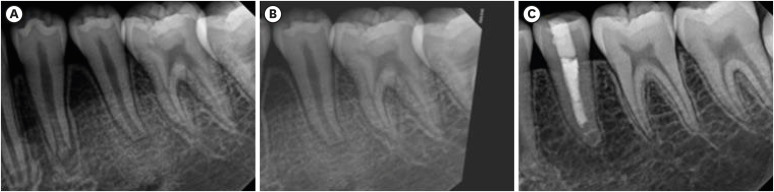

Abstract Image